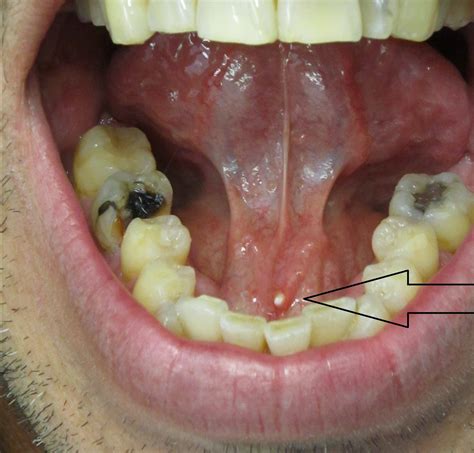

Your body has three main pairs of salivary glands: the parotid (near the cheeks), the submandibular (under the jaw), and the sublingual (under the tongue). Saliva is essential for digestion, keeping your mouth moist, and protecting your teeth from decay. A salivary gland stone forms when the chemicals in your saliva—such as calcium phosphate and calcium carbonate—crystallize and clump together. These hard, pebble-like stones can range in size from tiny specks to large, obstructive masses that significantly impede saliva production.

Most stones form in the submandibular glands, largely because the saliva produced there is thicker and the duct pathways are longer and more convoluted, making them more prone to blockages.

• Visible swelling under the tongue or near the jawline.